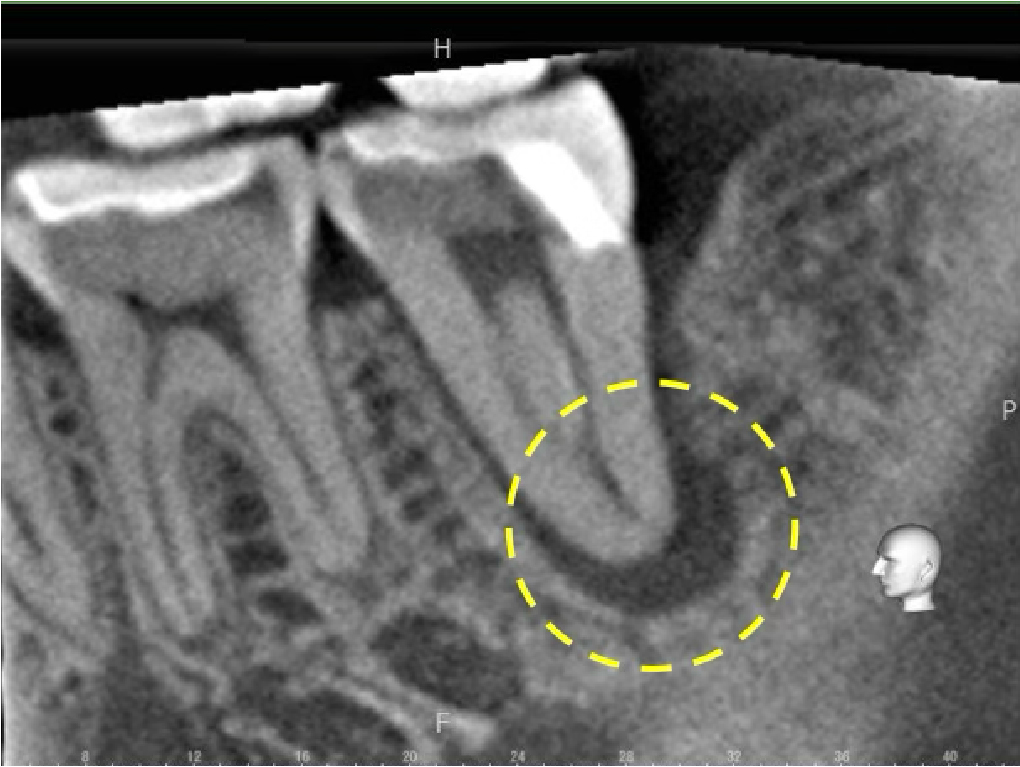

術後、3、6、12ヶ月の経過観察を行いました。6ヶ月時点では根尖部の透過像は残っていましたが、12ヶ月時点で根尖部の骨吸収像は消失し、良好な経過をたどっています。

歯茎の腫れ(フォステル)も、術後6ヶ月時点で消失しました。

今後、さらに長期にわたり、骨組織はより成熟していくことが予想されます。